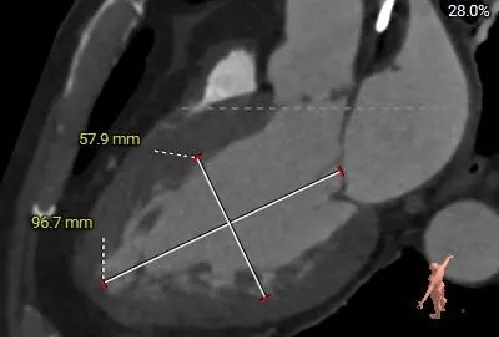

主动脉根部测量

Annulus:26.6mm

LVOT:29.3mm

钙化积分:0

SOV:

32.1*34.4*33.8mm

STJ:27.4mm

AAO:33.8mm

左室测量